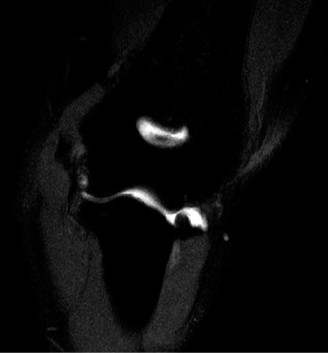

On examination, he has tenderness to palpation over his olecranon and pain with terminal elbow extension. He has no evidence of varus or valgus instability. No pain with resisted wrist flexion. His images are shown (Figs. 2–108 to 2–110).

Figure 2–110

The correct answer is (A). This syndrome occurs most commonly in competitive pitchers, with pain that is worse in the deceleration phase and at terminal extension. The resulting chronic stress results in chondrolysis, osteophyte formation, and attenuation of the MCL. Medial epicondylitis is also common in pitchers, but the pathology is limited to the flexor pronator mass. Pain is over the medial epicondyle and is worse with wrist and forearm flexion. OCD lesions are most common in the capitellum, often present with mechanical symptoms. Olecranon stress fractures result from repetitive abutment into the olecranon fossa. This is a plausible answer, however, the MRI findings are not consistent. MCL rupture is typically acute and is not seen on the MRI shown.